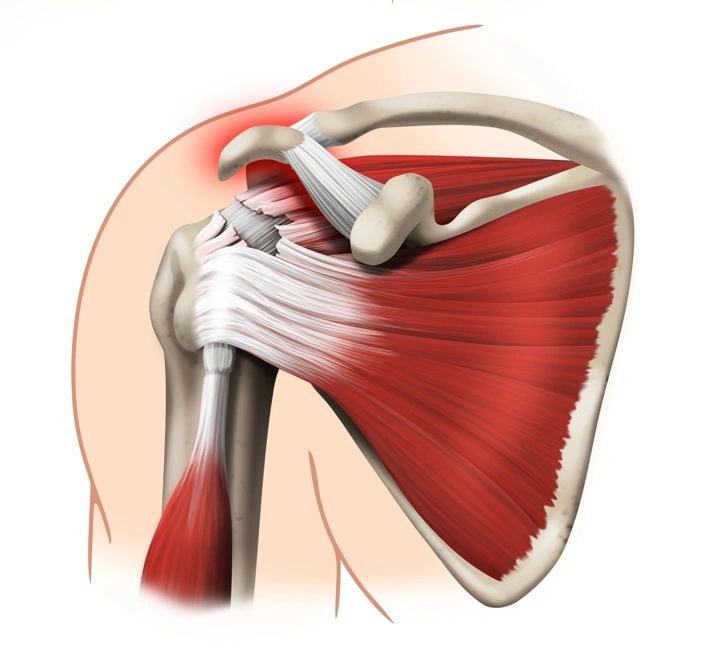

Фотографии мышц ротаторной манжеты плеча